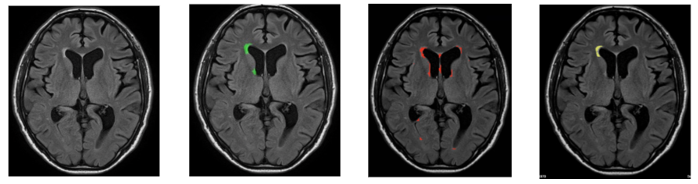

【新モデルによる解析結果例】

旧モデルの解析結果は、医師が作成した正解領域に比べて余分な領域を推論しているのに対し、新モデルでは医師が作成した正解領域により近い領域を出力しています。

(1) (2) (3) (4)

(1) 元画像 (2) 医師が作成した正解領域 (3) 旧モデルの解析結果 (4) 新モデルの解析結果